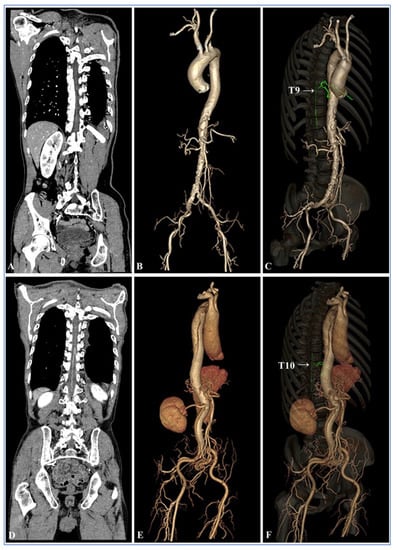

| Groups | Image Reconstruction Methods | Visualization Scores of the Adamkiewicz Arteries | Hairpin Curve | Branching Level | ||||

|---|---|---|---|---|---|---|---|---|

| 1 = Poor | 2 = Fair | 3 = Good | 4 = Fine | 5 = Excellent | ||||

| Group B | 120 kV FBP | 12 (24.0%) | 14 (28.0%) | 11 (22.0%) | 9 (18.0%) | 4 (8.0%) | 38 (76.0%) | 24 (48.0%) |

| Group A | 100 kV FBP | 5 (10.0%) | 9 (18.0%) | 16 (32.0%) | 12 (24.0%) | 8 (16.0%) | 45 (90.0%) | 36 (72.0%) |

| 100 kV ASIR-V 10% | 5 (10.0%) | 9 (18.0%) | 16 (32.0%) | 12 (24.0%) | 8 (16.0%) | 45 (90.0%) | 36 (72.0%) | |

| 100 kV ASIR-V 20% | 5 (10.0%) | 8 (16.0%) | 16 (32.0%) | 13 (26.0%) | 8 (16.0%) | 45 (90.0%) | 37 (74.0%) | |

| 100 kV ASIR-V 30% | 4 (8.0%) | 7 (14.0%) | 14 (28.0%) | 16 (32.0%) | 9 (18.0%) | 46 (92.0%) | 39 (78.0%) | |

| 100 kV ASIR-V 40% | 4 (8.0%) | 7 (14.0%) | 13 (26.0%) | 17 (34.0%) | 9 (18.0%) | 46 (92.0%) | 39 (78.0%) | |

| 100 kV ASIR-V 50% | 4 (8.0%) | 6 (12.0%) | 12 (24.0%) | 18 (36.0%) | 10 (20.0%) | 46 (92.0%) | 40 (80.0%) | |

| 100 kV ASIR-V 60% | 3 (6.0%) | 5 (10.0%) | 10 (20.0%) | 19 (38.0%) | 13 (26.0%) | 47 (94.0%) | 42 (84.0%) | |

| 100 kV ASIR-V 70% | 3 (6.0%) | 4 (8.0%) | 10 (20.0%) | 20 (40.0%) | 13 (26.0%) | 47 (94.0%) | 43 (86.0%) | |

| 100 kV ASIR-V 80% | 2 (4.0%) | 3 (6.0%) | 9 (18.0%) | 22 (44.0%) | 14 (28.0%) | 48 (96.0%) | 45 (90.0%) | |

| 100 kV ASIR-V 90% | 2 (4.0%) | 3 (6.0%) | 7 (14.0%) | 24 (48.0%) | 14 (28.0%) | 48 (96.0%) | 45 (90.0%) | |

| 100 kV ASIR-V 100% | 2 (4.0%) | 3 (6.0%) | 6 (12.0%) | 24 (48.0%) | 15 (30.0%) | 48 (96.0%) | 45 (90.0%) | |